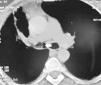

Case reportA 48-year old lady presented to the Chest Clinic with complaints of dry cough of six months duration. There was no history of fever, dyspnea, chest pain, wheeze or hemoptysis. She denied any addictions. Physical examination was unremarkable. Pulse oximetric saturation was 99% on room air. A chest radiograph was suggestive of volume loss in the right hemithorax (Fig. 1). Computed tomography (CT) of the thorax showed a low attenuation tumor in the right main bronchus suggestive of a fat containing lesion (Fig. 2). FB revealed the presence of a yellowish tumor with a smooth external surface causing near total occlusion of the right main bronchus (Fig. 3). The right upper lobe bronchus was not visualized and the bronchoscope could not be advanced into the right main bronchus. The patient was advised to have a rigid bronchoscopic removal of the tumor however she was not willing to have a general anesthesia.

DiscussionBenign endobronchial tumors present with clinical symptoms depending on the type of tumor (for e.g. most patients with carcinoid manifest with hemoptysis), extent of endobronchial obstruction, and the degree of distal parenchymal damage due to the obstruction.6,7 Lipomas constitute 3.2-9.5% of all benign endobronchial tumors.1 Nearly three-quarters of the patients are symptomatic and almost 80% have demonstrable chest radiographic abnormalities.6 The CT findings of the presence of a lesion with an attenuation of fat (−100 HU) and absence of enhancement following contrast administration is usually diagnostic of lipoma.4 Histologically, endobronchial lipomas are described by their primary mesenchymal component as hamartomatous, fibromatous, chondromatous, lipomatous, or leiomyomatous.8 The index case fits into the lipomatous variety. Squamous metaplasia may be seen in the overlying epithelium, as in the index case.9